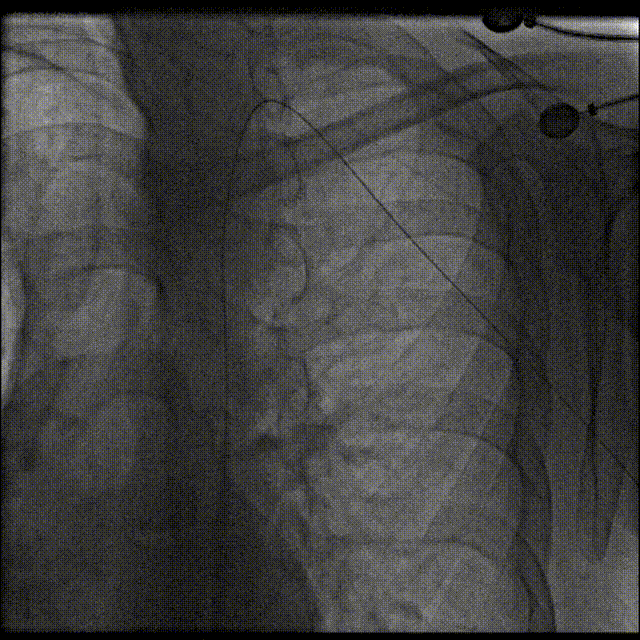

左锁骨下动脉送入圈套器抓捕Terumo软导丝,使导丝头端体外化,建立左桡动脉-弓离断-右股动脉导丝轨道,建立通路。

建立通路

6Fr Cook鞘和14Fr Cook鞘沿通路轻柔操作,先后对离断部位进行扩张。

鞘管扩张通路